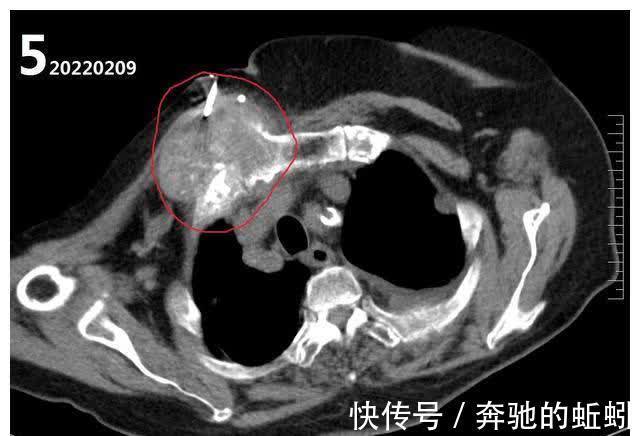

然后直到2022年2月9号才入院继续针对肺部病变进行针对性诊治。入院查胸部CT图4所示,肺部病灶较2021-12-9数目明显增多,安排了左肺病灶穿刺活检及胸壁肿物穿刺活检。

文章插图

活检结果肺内病灶考虑肺腺癌、胸壁肿物考虑转移性肿瘤。